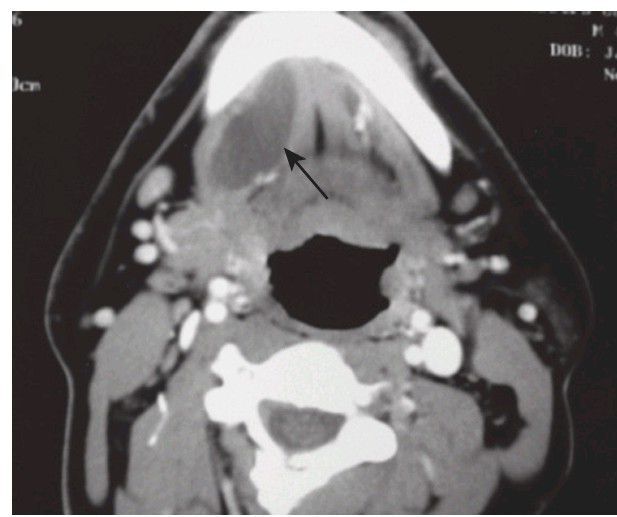

Right plunging ranula through the mylohyoid muscle seen on computed tomography scan (arrow)